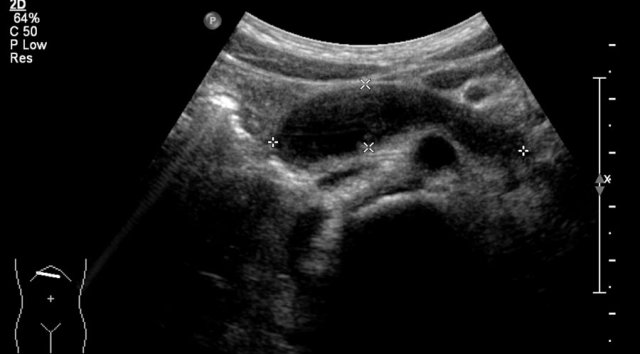

One-year-old boy was referred with a diagnosis of a cystic nephroblastoma.

Ultrasound detected a huge cyst in the middle of the abdomen.

When examined from the left flank with a high frequency linear array probe some parenchymal tissue was visible surrounding very dilated calyces. This is compatible with an extreme hydronephrosis.

At first it was thought that there were some solid parts in the cyst.

But when pressure was applied with the probe this proved to be debris.

MRI depicts the hydronephrosis with more overview.

The cause was a pyeloureteric stenosis.

The left kidney had 33% split renal function on renography.

A pyelum reconstruction was successfully performed.